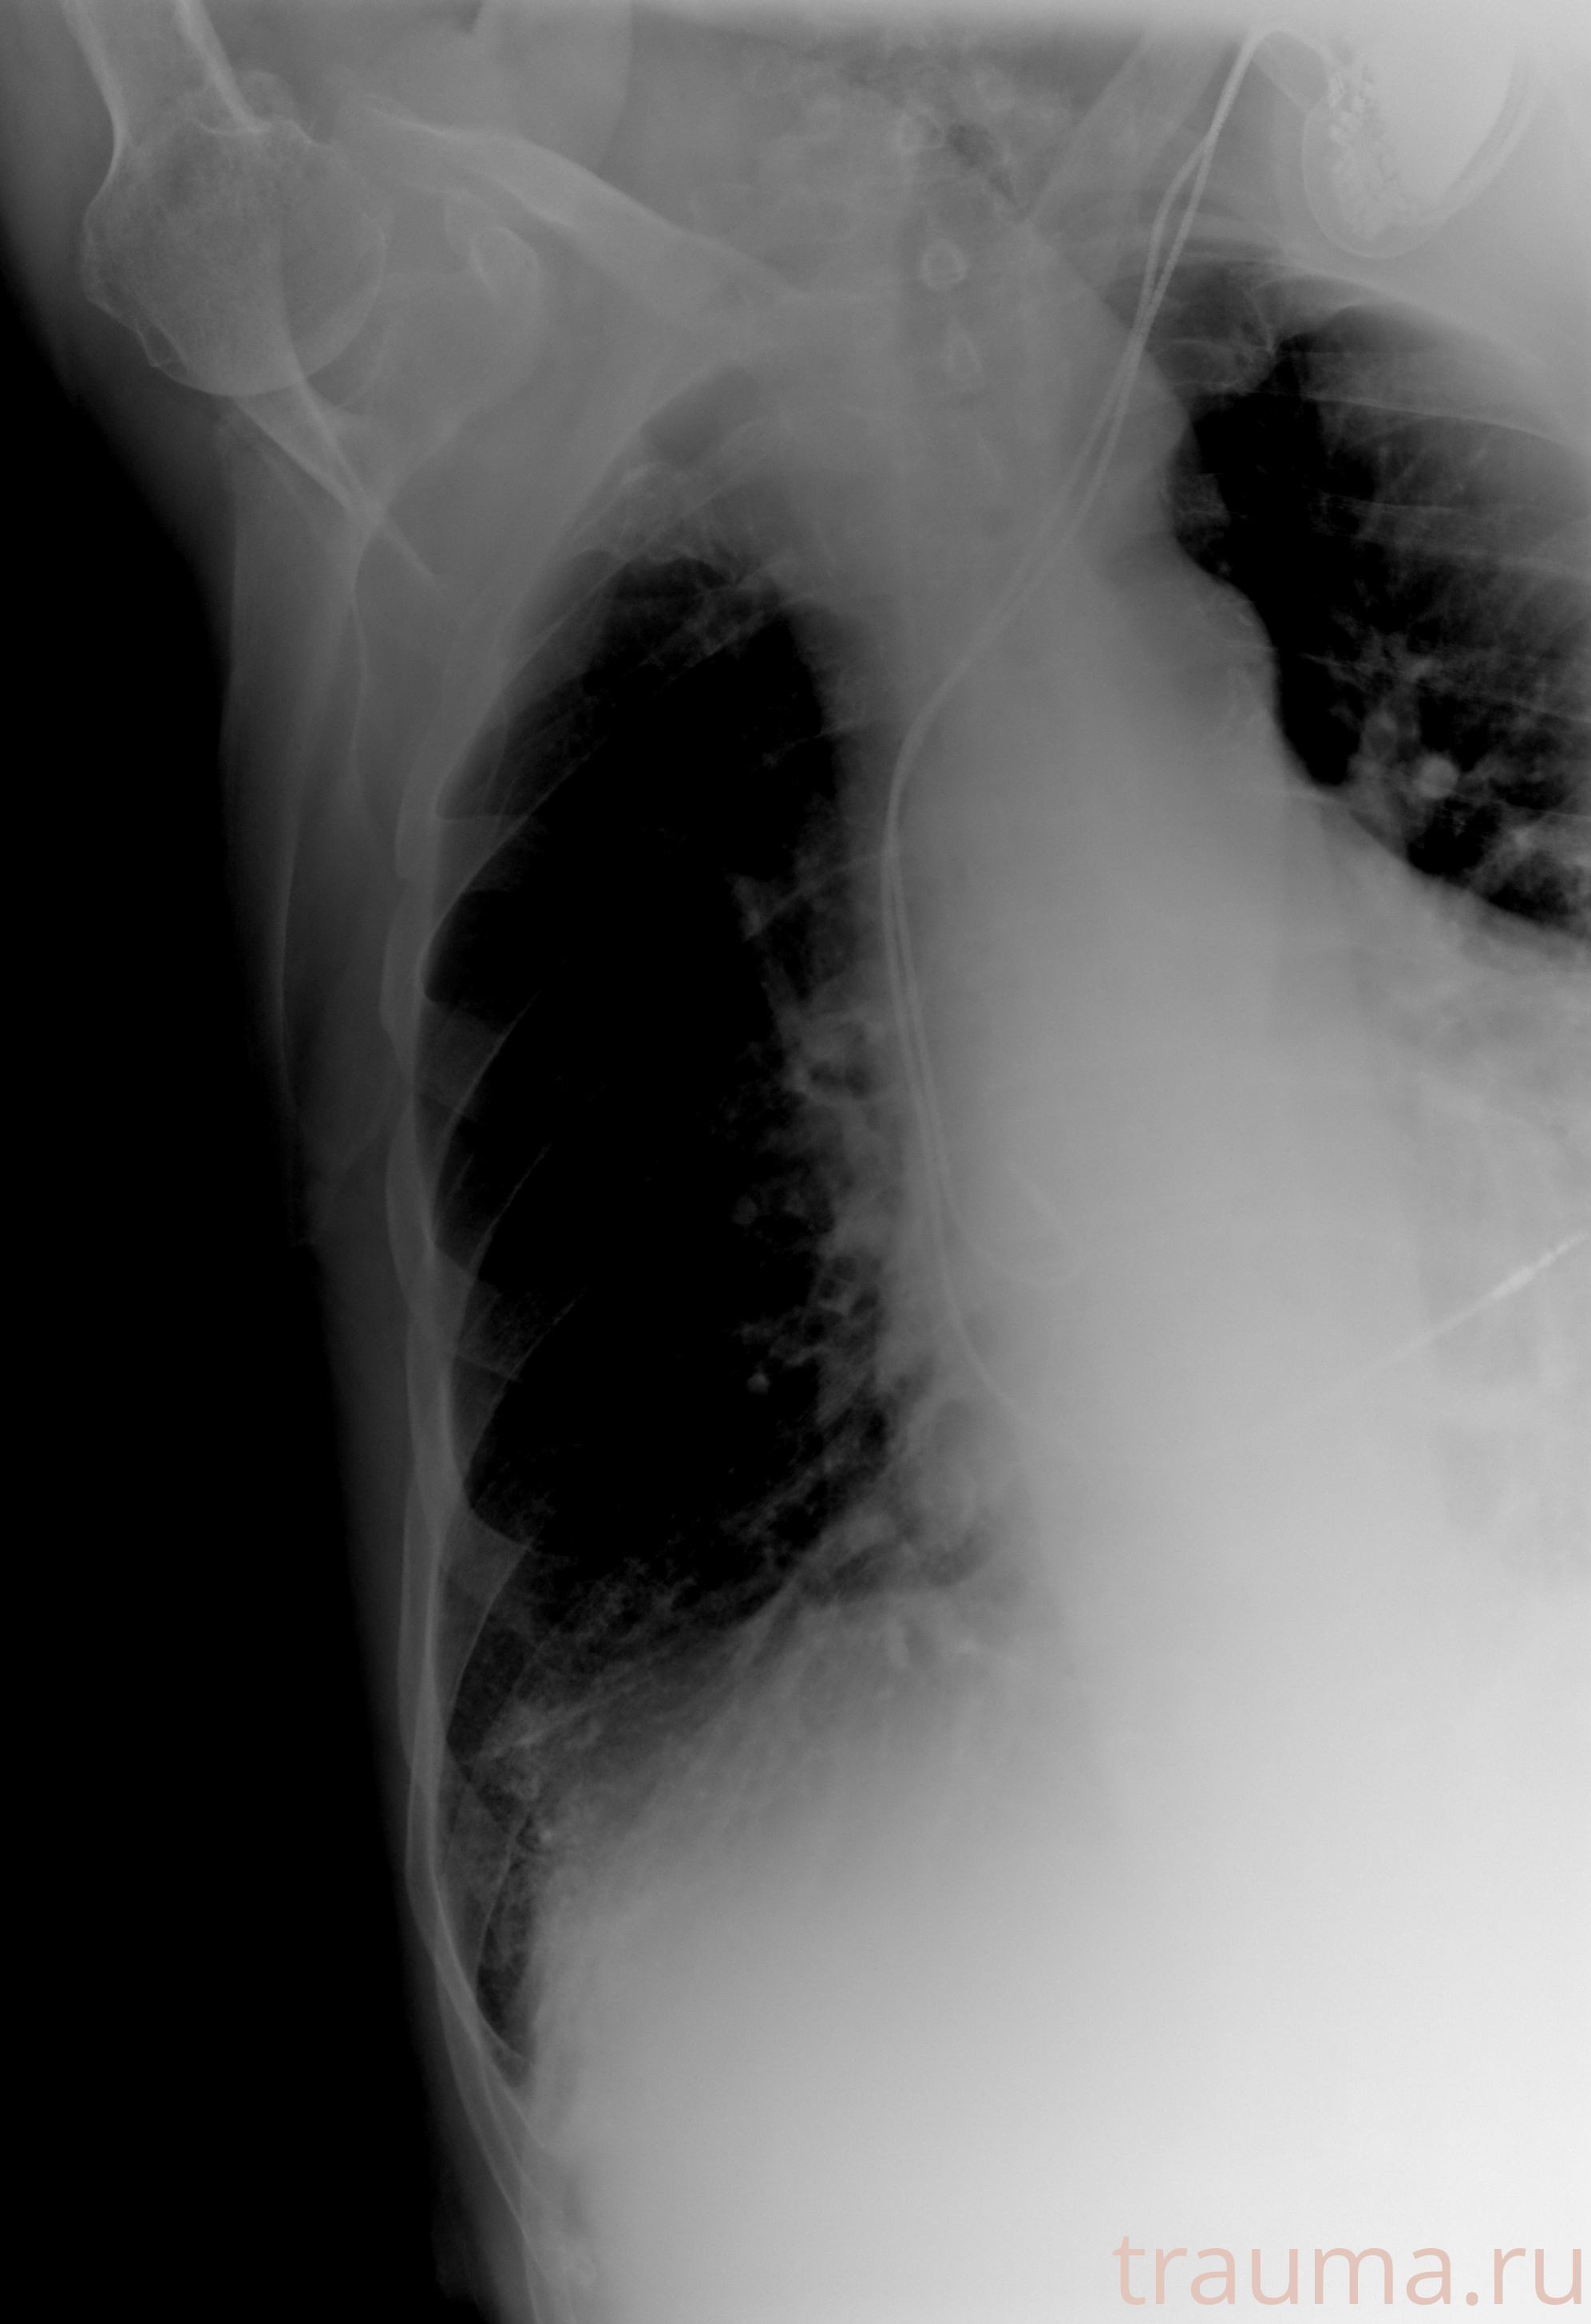

Рентген на дому: по вашему адресу приезжает врач-рентгенолог, травматолог-ортопед с мобильным рентгеновским аппаратом, проводит диагностику травмы или заболевания, делает необходимые рентгенограммы, дает рекомендации по дальнейшему лечению. Получить качественные снимки в домашних условиях возможно благодаря уникальной методике, разработанной МосРентген Центром для института  Склифосовского